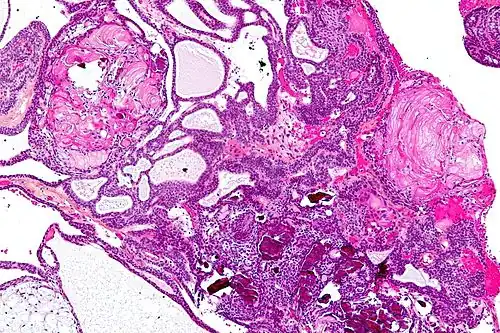

| Very low magnification micrograph of an adamantinomatous craniopharyngioma. HPS stain. | |

On macroscopic examination, craniopharyngiomas are cystic or partially cystic with solid areas. On light microscopy, the cysts are seen to be lined by stratified squamous epithelium. Keratin pearls may also be seen. The cysts are usually filled with a yellow, viscous fluid rich in cholesterol crystals. Of a long list of possible symptoms, the most common presentations include headaches, growth failure, and bitemporal hemianopsia.

Micrograph showing the characteristic features of an adamantinomatous craniopharyngioma - cystic spaces, calcifications, and "wet" keratin, HPS stain -

Micrograph showing a papillary craniopharyngioma, HPS stain